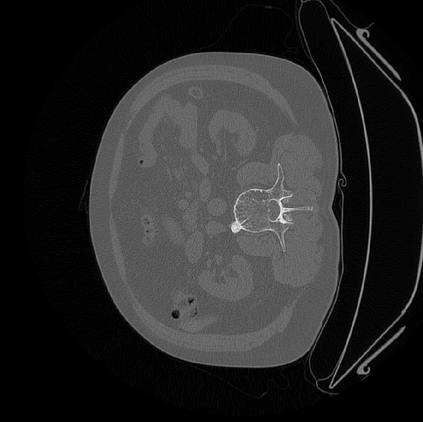

Deep Convolutional Neural Networks (DCNNs) are used extensively in medical image segmentation and hence 3D navigation for robot-assisted Minimally Invasive Surgeries (MISs). However, current DCNNs usually use down sampling layers for increasing the receptive field and gaining abstract semantic information. These down sampling layers decrease the spatial dimension of feature maps, which can be detrimental to image segmentation. Atrous convolution is an alternative for the down sampling layer. It increases the receptive field whilst maintains the spatial dimension of feature maps. In this paper, a method for effective atrous rate setting is proposed to achieve the largest and fully-covered receptive field with a minimum number of atrous convolutional layers. Furthermore, a new and full resolution DCNN - Atrous Convolutional Neural Network (ACNN), which incorporates cascaded atrous II-blocks, residual learning and Instance Normalization (IN). Application results of the proposed ACNN to Magnetic Resonance Imaging (MRI) and Computed Tomography (CT) image segmentation demonstrate that the proposed ACNN can achieve higher segmentation Intersection over Unions (IoUs) to U-Net and Deeplabv3+, but with significantly reduced trainable parameters.